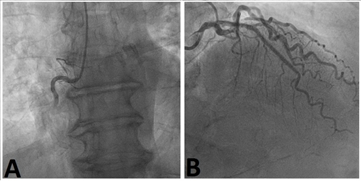

Six days after primary PCI, the patient was brought back to the cath lab; engagement of RCA was performed with 6 French Amplatz Right 1.0 guiding catheter through left radial artery access. The coronary angiography confirmed a severe calcific thigh stenosis of the mid RCA and severe stenosis of the distal vessel segment. Using the new RotaPro Rotational Atherectomy System (Boston Scientific Corp.), RA was executed with the 1.5mm burr, advanced on the 0.009-inch floppy RotaWire guidewire (Boston Scientific Corp.), from proximal to the distal segment of RCA. Patient did not become hypotensive during the procedure, maintaining normal vital parameters. Then, multiple dilatations with 2.5/15mm AngioSculpt scoring balloon (AngioScore, Inc., Fremont, California, USA) and 3.0/20mm semi-compliant balloon were performed. Finally, five durable-polymer Everolimus eluting stents (Xience; Abbott Vascular, Santa Clara, California, USA) were implanted in overlapping from distal to proximal RCA (respectively: 2.5/22mm, 2.5/22mm, 2.75/26mm, 3.0/26mm, 3.5/38mm), with subsequent stent-deployment optimization using 3.0/20mm and 3.5/20mm non-compliant balloons, achieving an optimal angiographic result (Figure 3). The patient was discharge after 4days in good clinical health condition.

Figure 3 Rota-staged procedure to optimize the angiographic result using Rotational Atherectomy A) Angiogram showing the residual heavily calcified lesion of right coronary artery in a left anterior oblique projection; B, C, D) Fluoroscopy images showing the use of rotational atherectomy into the right coronary artery, from proximal to distal segment; E) Fluoroscopy images showing the balloon dilatation of the right coronary artery; F) Angiogram showing the final result with a totally patent right coronary artery after stent implantation and post-dilatation, with a TIMI 3 flow.